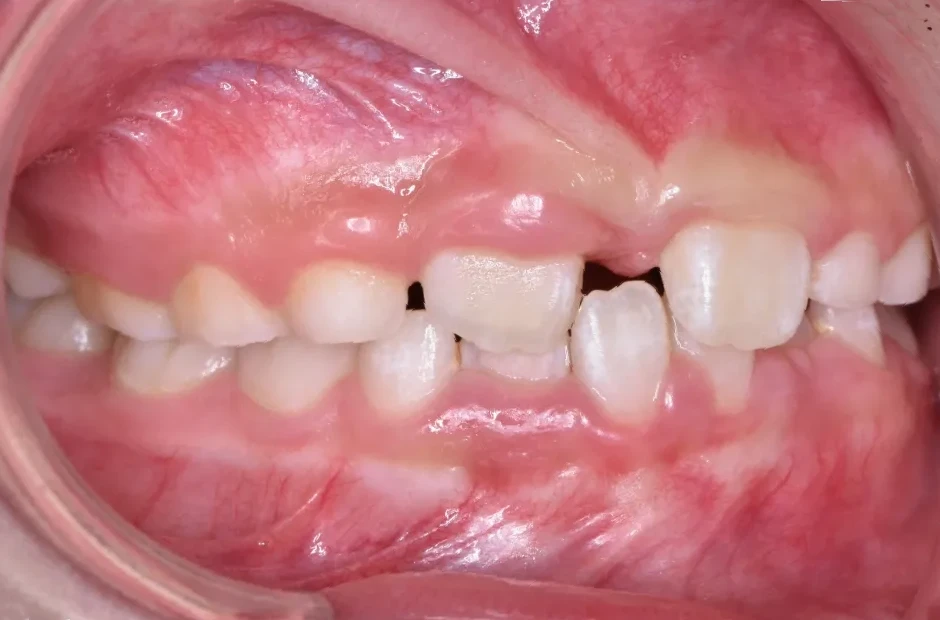

治療症例

ブラケット矯正

前歯部反対咬合

| 診断名・主訴 | 前歯部反対咬合 |

|---|---|

| 年齢・性別 | 14歳・男性 |

| 治療期間・回数 | 1年2か月 |

| 治療に用いた主な装置 | ブラケット矯正 |

| 抜歯部位 | なし |

| 治療費 | 60万円(税抜) |

| リスク・副作用 | 装置による違和感・疼痛・歯肉退縮・歯根吸収・虫歯のリスクなど |

治療前